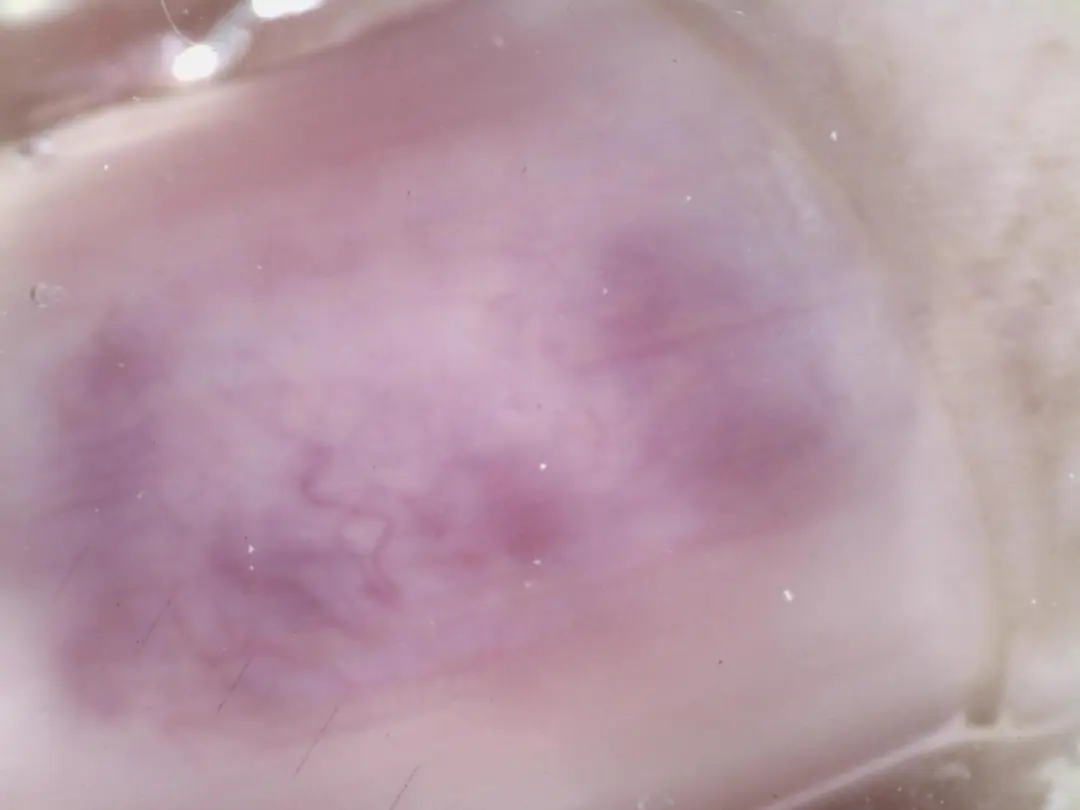

皮肤镜特征:

甲下可见边界清晰的紫红色或暗红色均质斑,直径多为 2-5mm,呈圆形或椭圆形,是肿瘤血管丰富的直接体现;

按压皮肤镜探头时,患者疼痛明显加剧(“疼痛诱发征”),斑片颜色暂时变浅;

部分病例可见甲板局部隆起或变形,无色素沉着或角质堆积。

诊断价值

皮肤镜下 “紫红色均质斑 + 疼痛诱发征” 具有高度特异性,可与甲下出血(颜色随时间变浅,无持续疼痛)、甲下黑色素瘤(有不规则色素条纹)鉴别。皮肤镜检查可避免不必要的有创活检,直接指导手术切除。